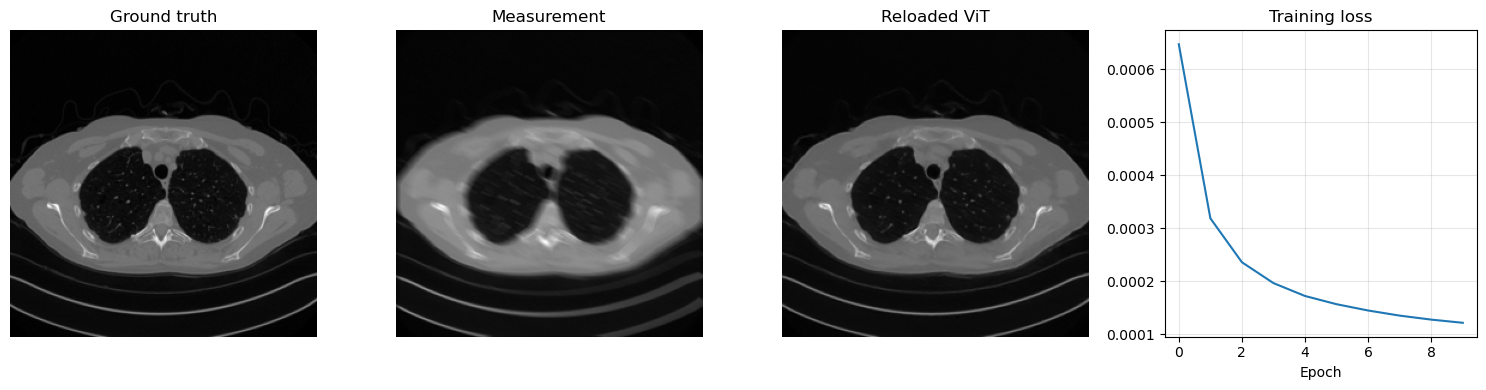

The same supervised strategy used for CNNs and residual CNNs can be applied to a ViT-based reconstructor. We again generate motion-blurred and noisy measurements from the clean Mayo slices, train the model with MSELoss, and then save the learned parameters in ../weights/ViT.pth. The code also reloads the checkpoint immediately, so the save/load pattern remains explicit.

plt.figure(figsize=(15, 4))

plt.subplot(1, 4, 1)

plt.imshow(x_test.cpu().squeeze(), cmap='gray')

plt.title('Ground truth')

plt.axis('off')

plt.subplot(1, 4, 2)

plt.imshow(y_test.cpu().squeeze(), cmap='gray')

plt.title('Measurement')

plt.subplot(1, 4, 3)

plt.imshow(x_pred.cpu().squeeze(), cmap='gray')

plt.title('Reloaded ViT')

plt.subplot(1, 4, 4)

plt.plot(history)

plt.title('Training loss')

plt.xlabel('Epoch')

plt.grid(alpha=0.3)

plt.tight_layout()

plt.show()